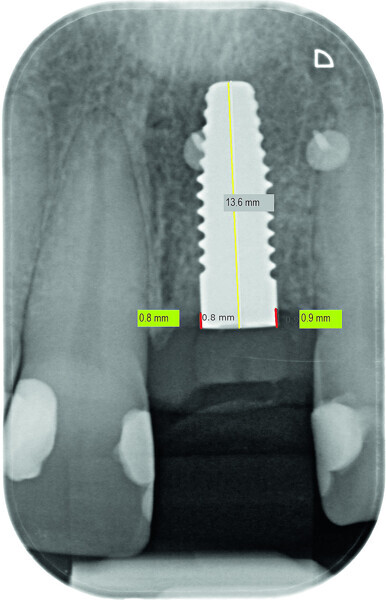

Fig. 13a: Bone resorption was detected after six months and bone gain after 12 months. The yellow line represents the actual implant length (13.6mm). The red lines indicate the mesial and distal distances from the top of the implant to the first bone contact.